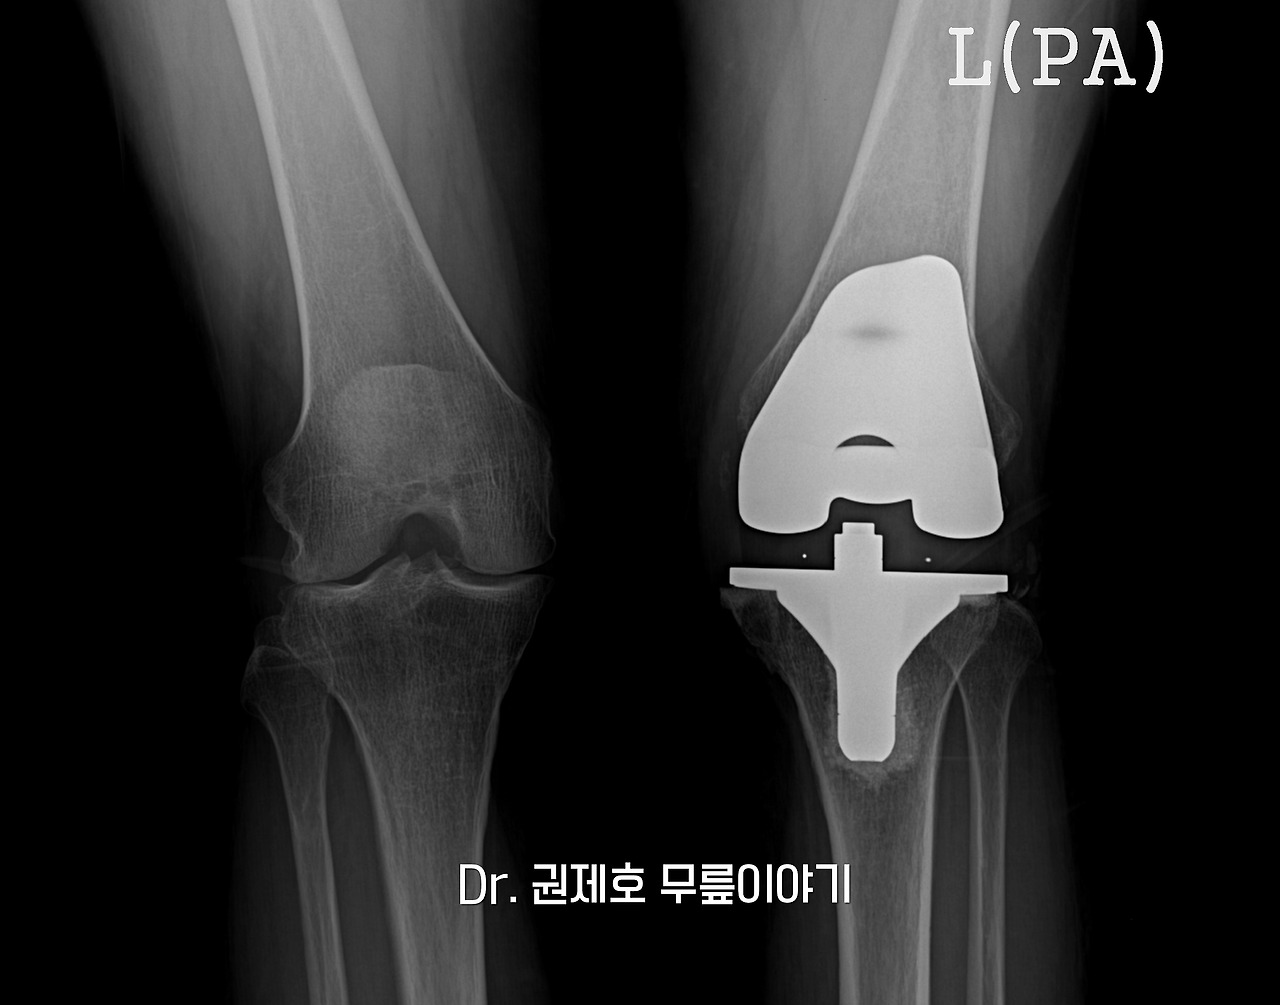

퇴행성관절염 인공관절 수술 과정 (9).jpg

로젠버그 사진도 촬영한다. 관절을 대신하는 인공관절의 모습과 뼈와 잘 어우러졌는지 그리고 연골을 대신하는 bearing의 위치도 확인하게 된다.